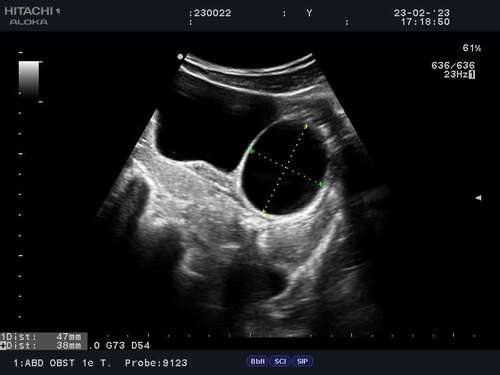

Mijn cyste was volgens mij 4,7 x 3,8 cm en kromp langzaamaan.

Bijgevoegd de foto! Ik was toen 7+5 weken zwanger.